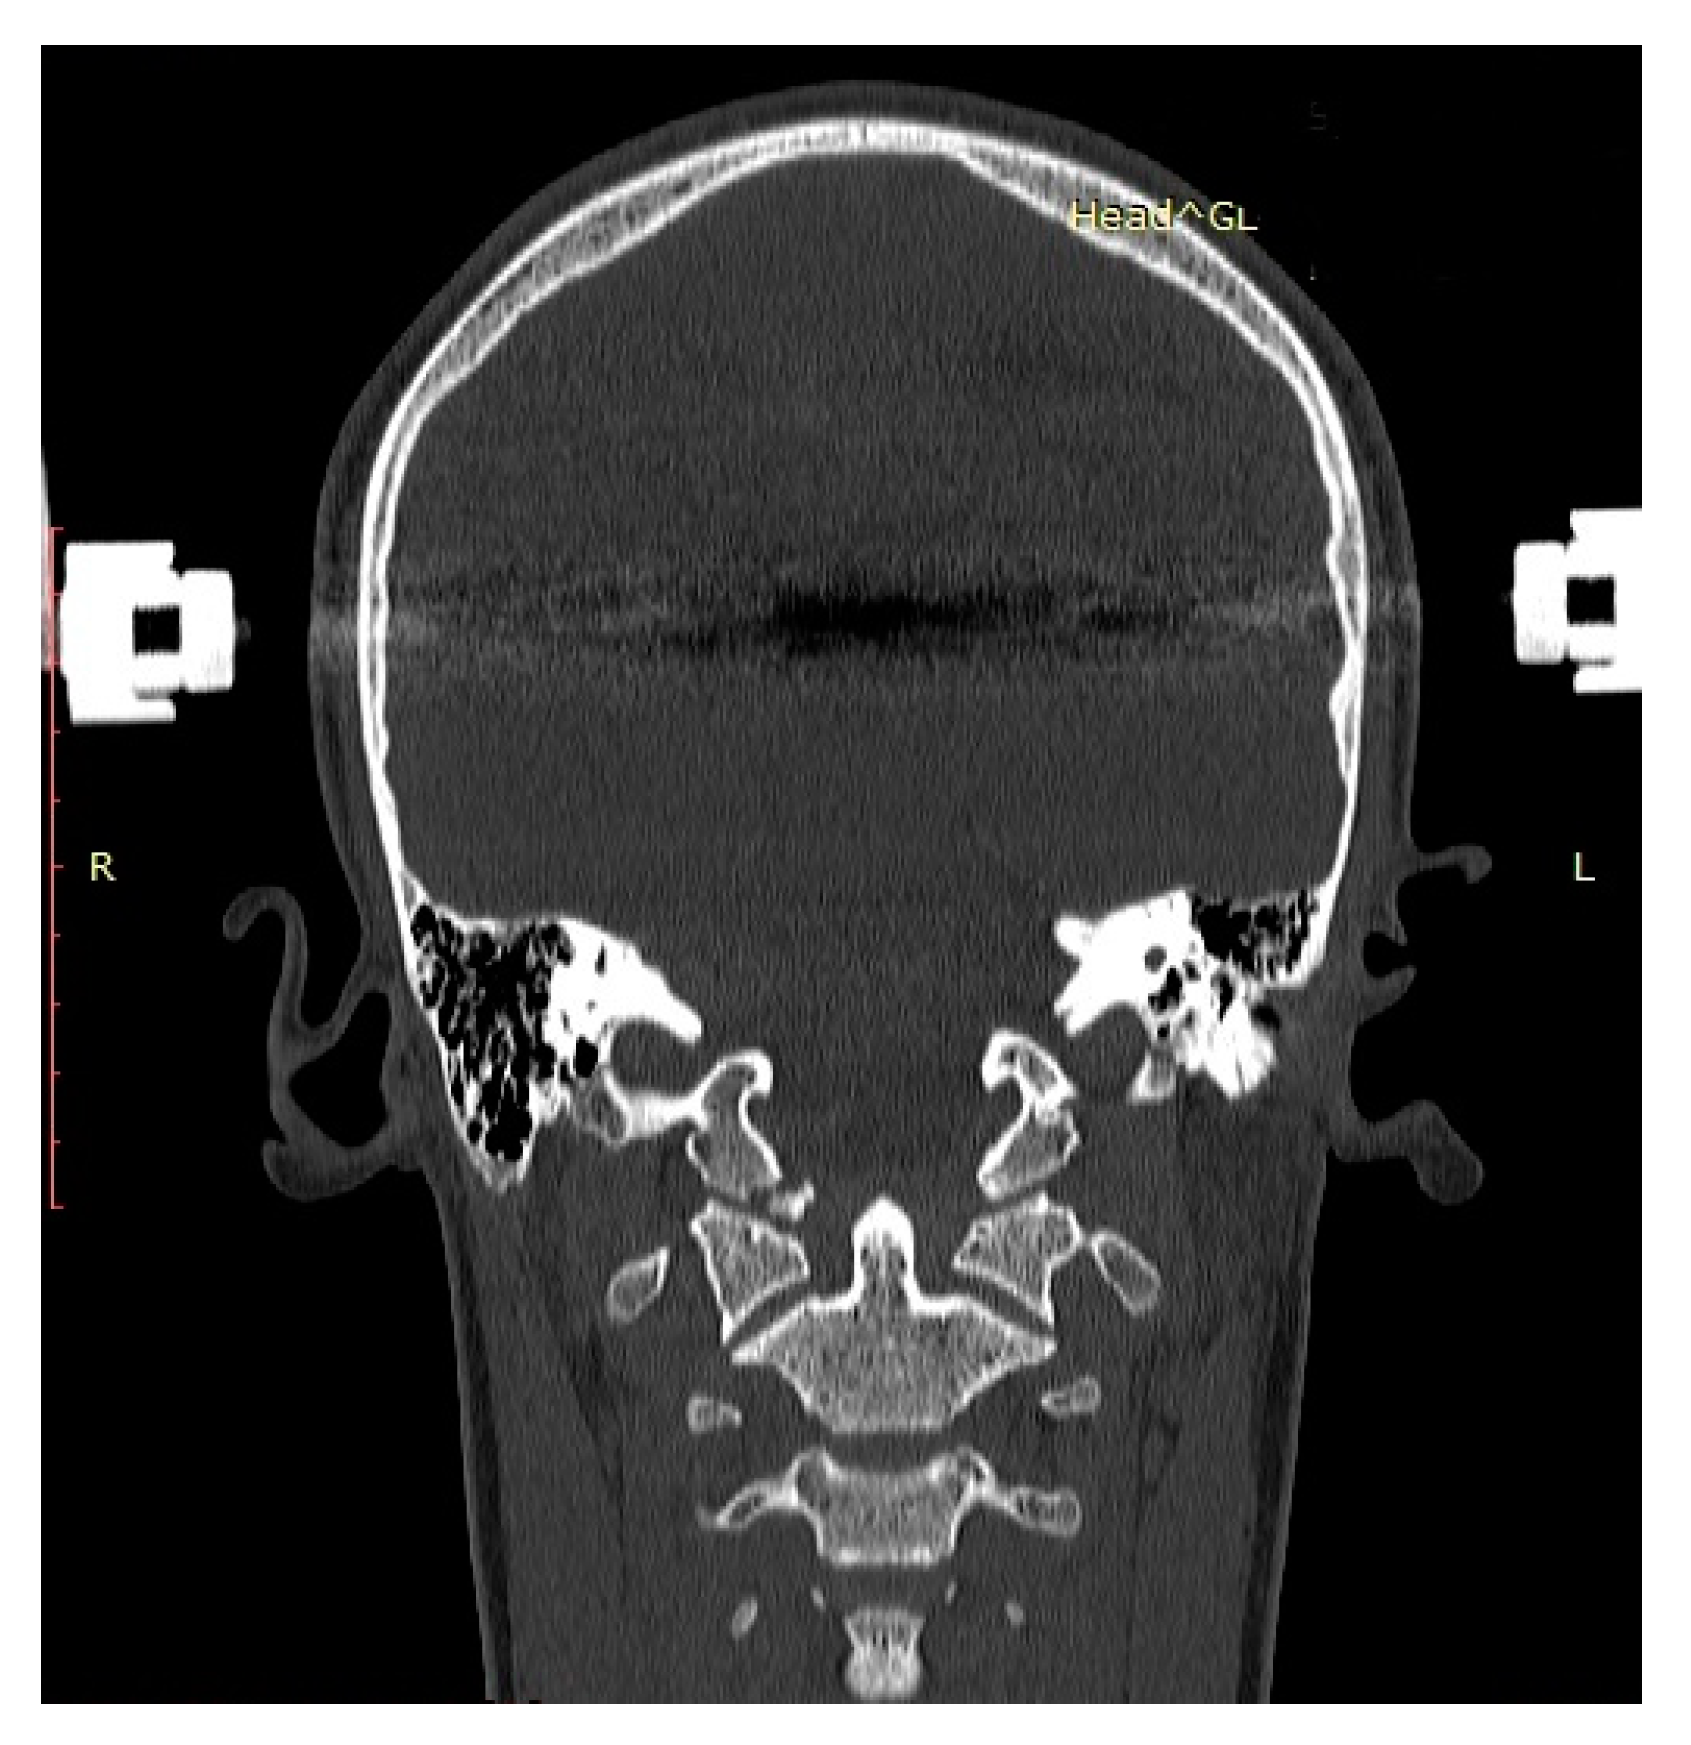

- We recommend CT and MRI of the CCJ to diagnose OCF and confirm post-therapeutic fracture consolidation in pediatric patients.

| Name (Initials) | Sex (Male/ Female) | Age (Years) | Anderson Montesano Classification | Tuli Classification | Cause of Injury | Accompanying Injuries | Immobilization Method |

|---|---|---|---|---|---|---|---|

| P.P. | M | 15.2 | III (unstable) | IIB | Road traffic accident (car passenger) | Fracture frontal bone, fracture frontal sinus, contusion of frontal lobe | Halo-vest immobilization: 12.5 weeks |

| K.D. | F | 15 | III (unstable) | IIB | Pedestrian hit by car | Lung contusion, brain concussion, multiple abrasions | Halo-vest immobilization: 13 weeks |

| R.M. | F | 18 | I (unstable) | IIB | Road traffic accident (car passenger) | Pneumothorax, neurogenic vocal cord injury, post-traumatic aphasia | Halo-vest immobilization: 14 weeks |

| S.D. | M | 14.7 | III (stable) | IIA | Road traffic accident (car passenger) | Fracture of frontal bone, fracture of nasal bone, subdural hematoma | Minerva-brace immobilization |

| B.W. | F | 16 | I (stable) | IIA | Fall from a height | Fracture of frontal bone, fracture of nasal bone, subarachnoid hemorrhage, fracture of transverse process Th3-5, fracture of radius | Minerva-brace immobilization |

| M.O. | M | 16.1 | I (stable) | IIA | Bicycle incident | Fracture frontal bone, fracture maxillary sinus, fracture orbit, metacarpal fracture | Minerva-brace immobilization |